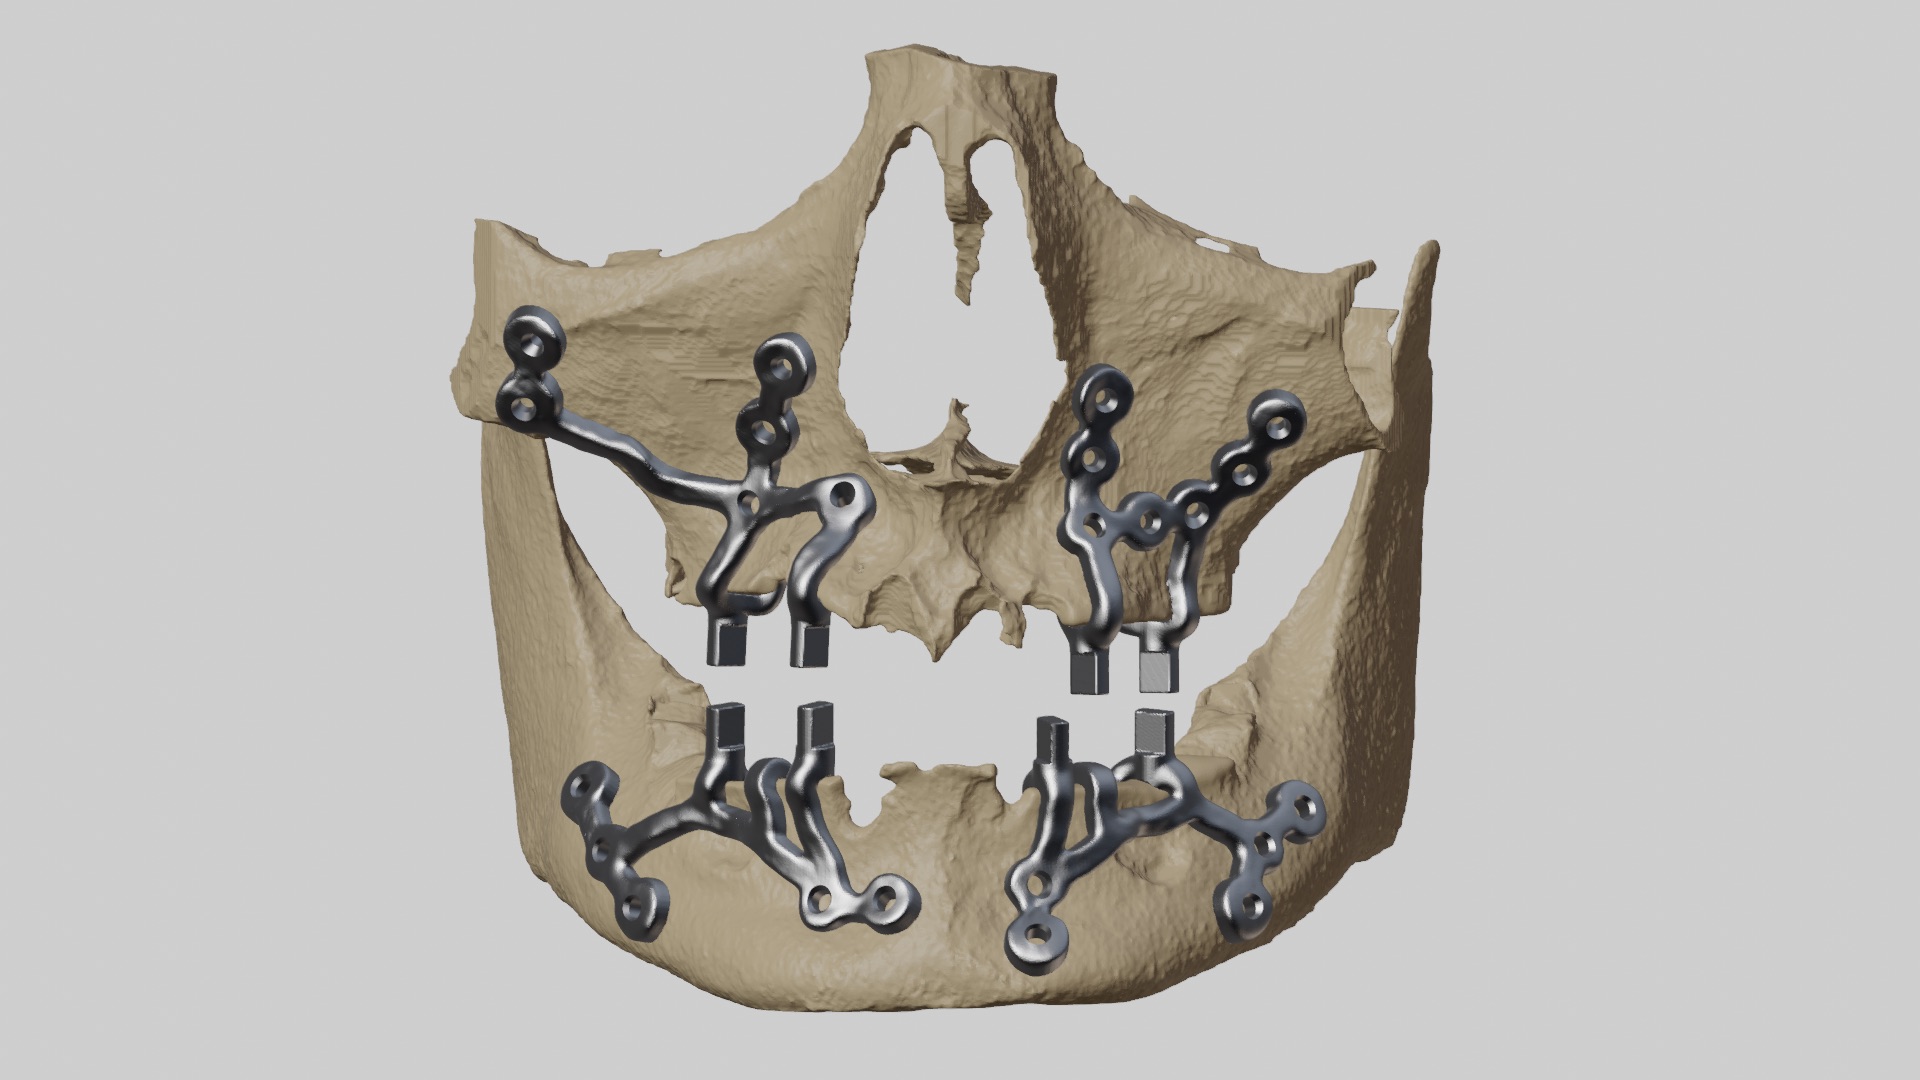

Custom-designed, 3D-printed subperiosteal titanium implant system

- CBCT-based 3D reconstruction

- CAD-based virtual implant design

- Finite Element Analysis (FEA) for stress distribution assessment

- Manufacturing using Titanium Ti6Al4V alloy via Direct Metal Laser Sintering (DMLS)

- Passive adaptation of custom subperiosteal implant framework

- Fixation using titanium screws (multiple anchorage points)